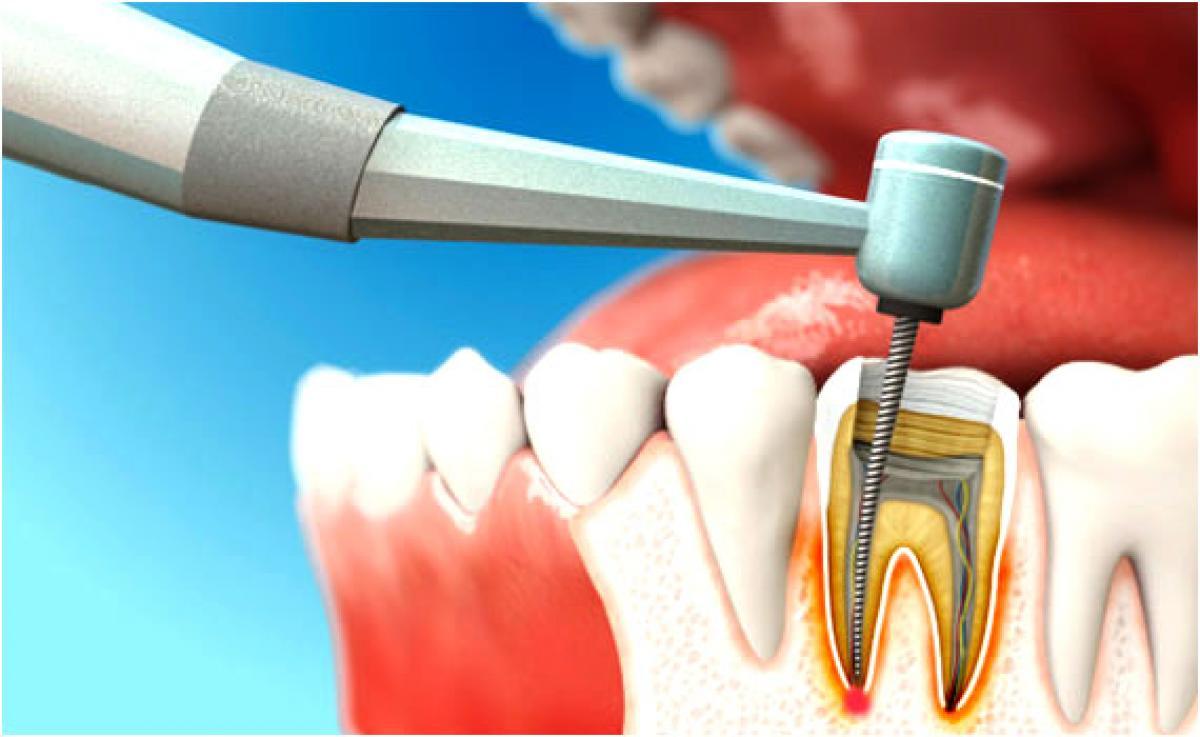

Реплантация зуба: Этапы и особенности операции